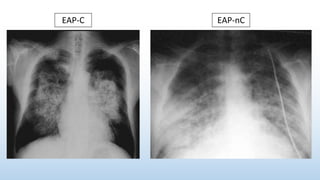

Parámetros EAP Cardiogénico EAP não Cardiogénico

Episódio Cardiaco Agudo Habitualmente presente Não frequente (mas possível)

Débito Cardiaco Baixo fluxo (pele fria) Fluxo alto(pele quente, pulso cheio)

Galope x S3 Presente Ausente

PVJ Presente Ausente

Fervores Húmidos Secos

Doença subjacente Habitualmente ausente Presente

ECG Isquemia / Enfarto Habitualmente normal

Rx de Tórax Distribução perihilar Distribução periférica

Enzimas cardiacas Podem estar elevadas Habitualmente normais

ExploraçãoFísicaLaboratório

Diferenças entre EAP Cardiogénico e Não Cardiogénico

EAP-C EAP-nC